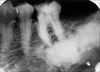

Well-defined apical radiolucency with loss of lamina dura – diagnosis?

• Periodontitis periapicalis chronica granulomatosa

• (chronic granulomatous apical periodontitis).

• Treatment: RCT or extraction